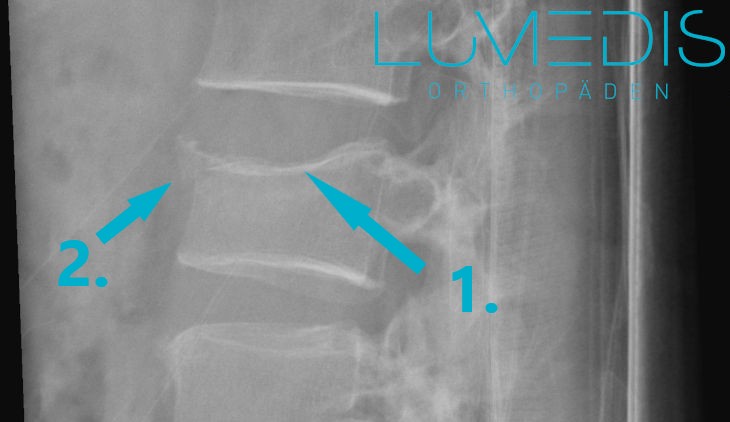

Abbildung eines Wirbelbruchs

Bei einer Deckplattenimpression bricht nur die Deckplatte des WIrbelkörpers, in aller Regel nur die vordere Oberseite des Wirbelkörpers.

Die Boden-, bzw. Grundplatte bleibt dabei meist ohne Bruch.

Eine Deckplattenimpression ist in der Regel eine stabile Fraktur.

CT eines Wirbelbruchs der LWS seitlich